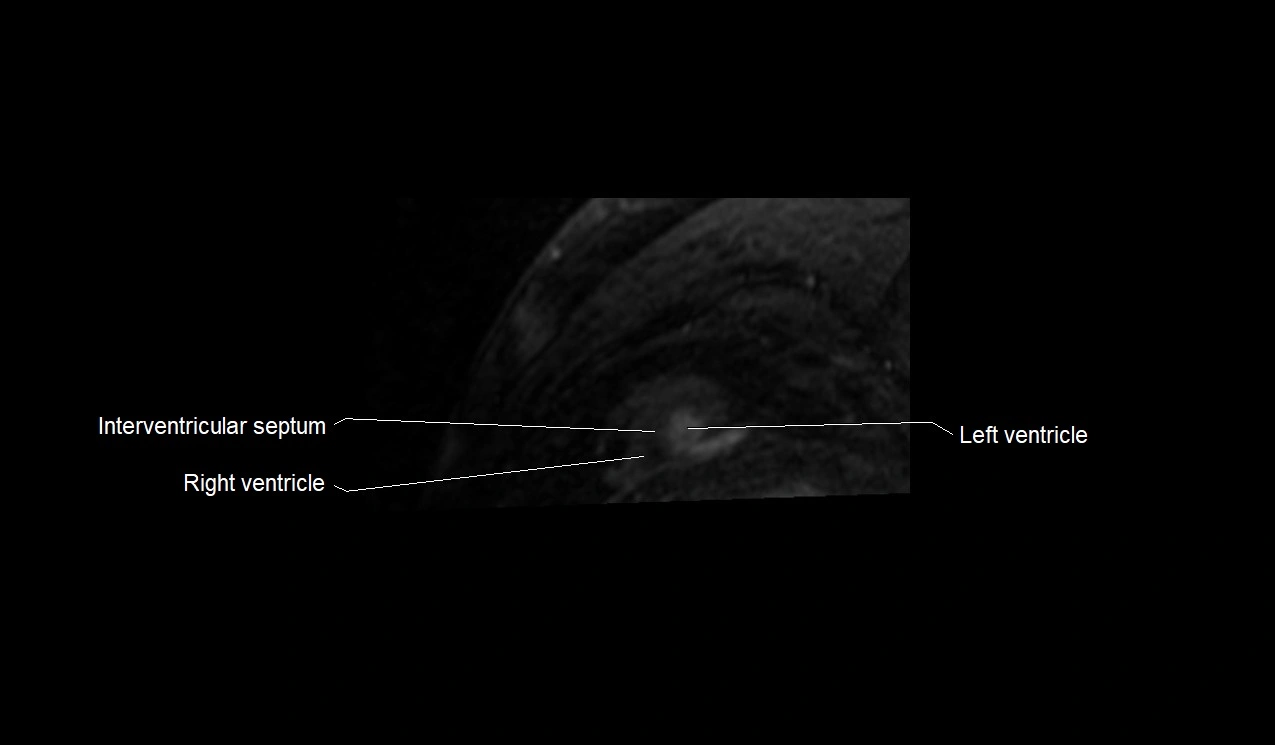

MRI image